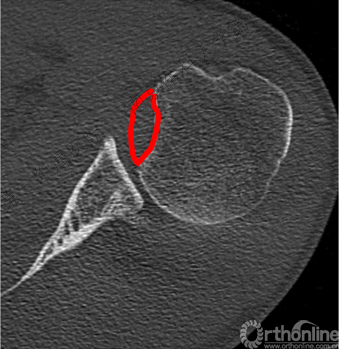

了解反Hill-sachs损伤和程度。

1.反Hill-Sachs损伤范围对肩关节后方稳定性具有决定性的影响。

(五)修复反Hill-Sachs损伤

1.外旋肱骨头,显露肱骨头关节面损伤处。

2.改良McLaughlin术、 Underpinning术、球囊扩张术。

3.Dubousset 方法:对肱骨头关节面压缩性骨折均给予直视下复位、填充植骨、螺钉固定,手术指征不受压缩部分占总关节面面积比例的限制。